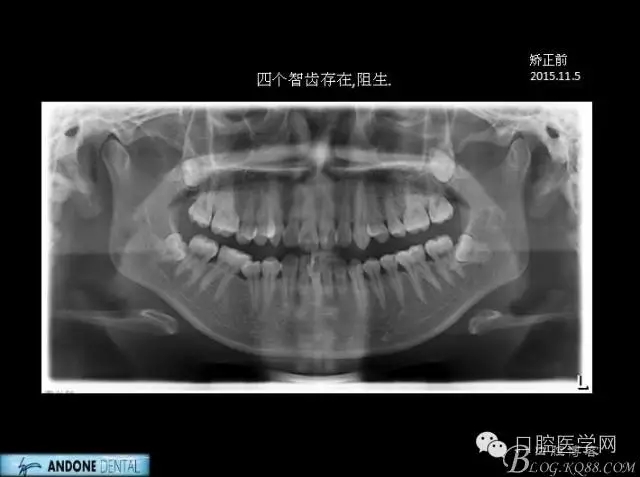

直面型下中度擁擠的不拔牙矯治